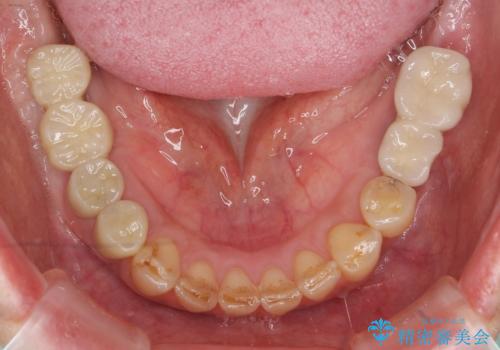

- 痛くて噛めない、これまでだましだまし治療をしてきたがこれを機にすべてきっちりと治したい、口の中の悩みを解決したいと来院されました。

抜歯や歯周病治療、欠損補綴を含め、全顎的な治療を計画・提案します。

口腔内に歯の破折や歯周病、虫歯、欠損など複数の問題が存在する場合局所的に問題を解決していくのではなく全顎的な治療を行っていくことで長期的な予後を見込むことができます。